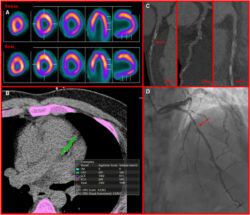

Published in Pacing and Clinical Electrophysiology (PACE), the research, “Uncovering the Structural Effects of Radiofrequency Ablation on the Papillary Muscle–Chordae Tendineae Junction,” examines how RF ablation impacts tissue strength and integrity in one of the heart’s most delicate structures.

The team’s findings suggest that while RF ablation remains an effective therapy for treating ventricular arrhythmias, it can induce microscopic changes in cardiac tissue that warrant further study to optimize procedural safety and reduce potential complications. This foundational research sets the stage for future in vivo studies to explore how these changes evolve during healing and how catheter design might improve force detection during ablation.